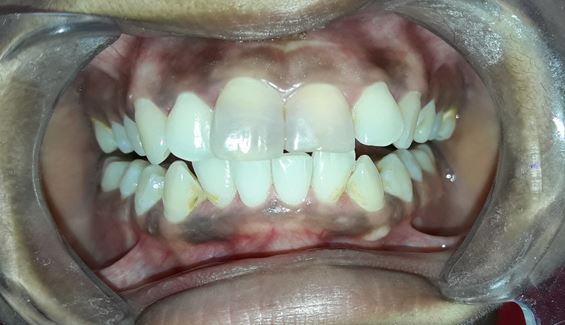

Management of intrinsic discoloration using walking bleach technique in maxillary central incisors

Introduction. Non-vital bleaching is a non-invasive technique to treat the intrinsic discoloration of teeth of several etiologies. Hydrogen peroxide and sodium perborate are commonly used bleaching agents.

Aim. The aim of this case report is to demonstrate the non-vital bleaching technique in maxillary anterior teeth.

Method. Maxillary central incisors were isolated with rubber dam and root canal treatment was performed. Barrier space preparation was done using a heated instrument. Glass ionomer cement was used a barrier material. Mixture of hydrogen peroxide and sodium perborate was placed in the canal and sealed with intermediate restorative material. After 1 week, the procedure was repeated to achieve the desired results.